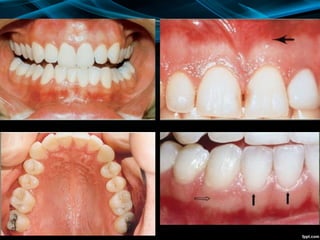

Gingiva (Gum(

1. Attached gingiva: It is firmly bound to the

2. Free or unattached gingiva: It is the distal 1

mm margin of gingiva that surrounds the neck

of the tooth and is not attached to the bone.